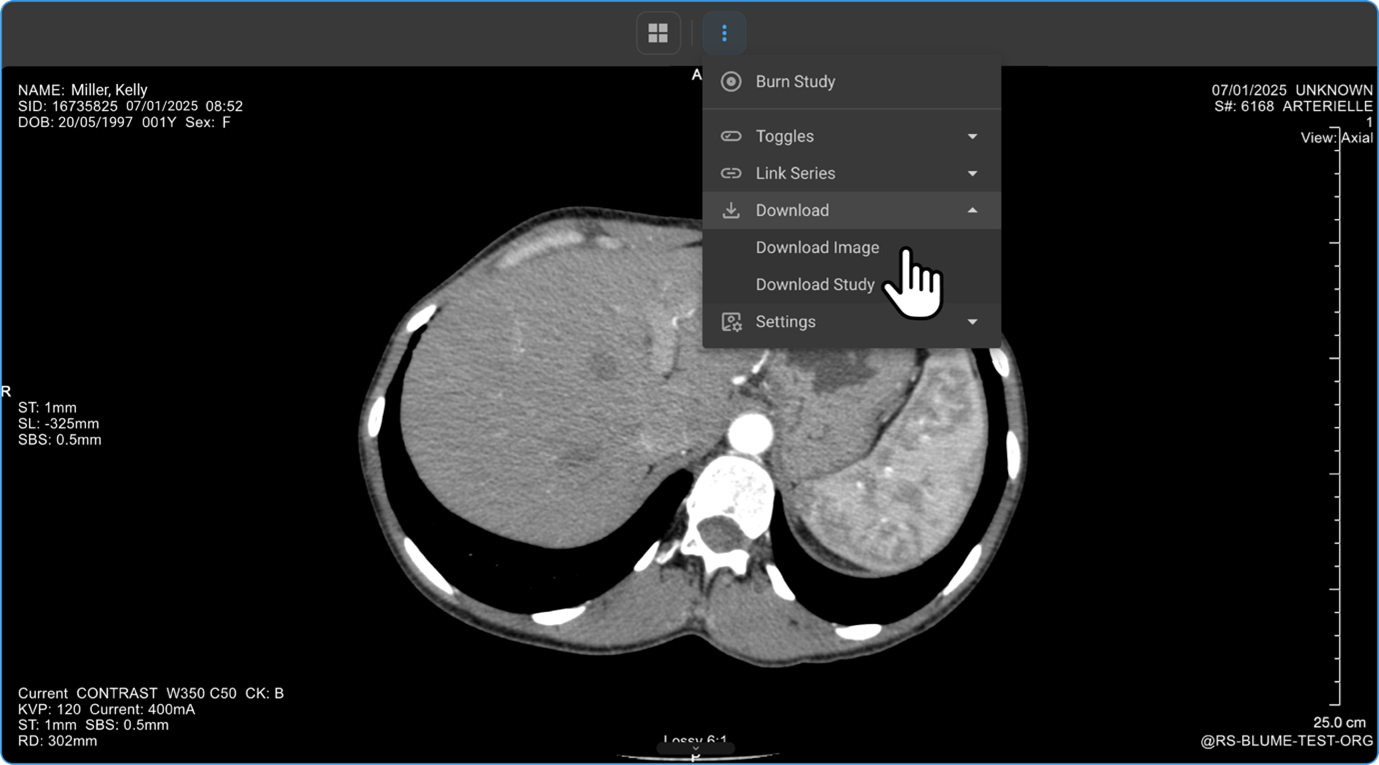

What’s in the More Options (⋮) Ellipsis Drawer Options Menu?

Click the three dots (⋮) on the toolbar to access advanced features:

Downloading Images from the Image Viewer

-

Click View Images to open the Image Viewer.

Click the three-dot menu (⋮) in the viewer toolbar.

Select Download → Download Image or Download Study.

Enter the file name and preferred image resolution (in pixels), then click Download.